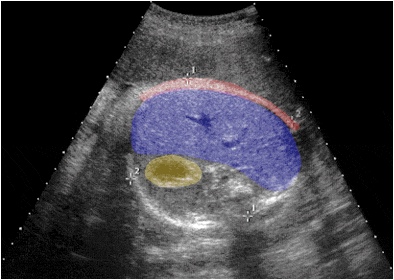

Ecografía fetal que muestra en un corte transversal el higado (azul), el estomago (amarillo) y la pared abdominal (rojo).